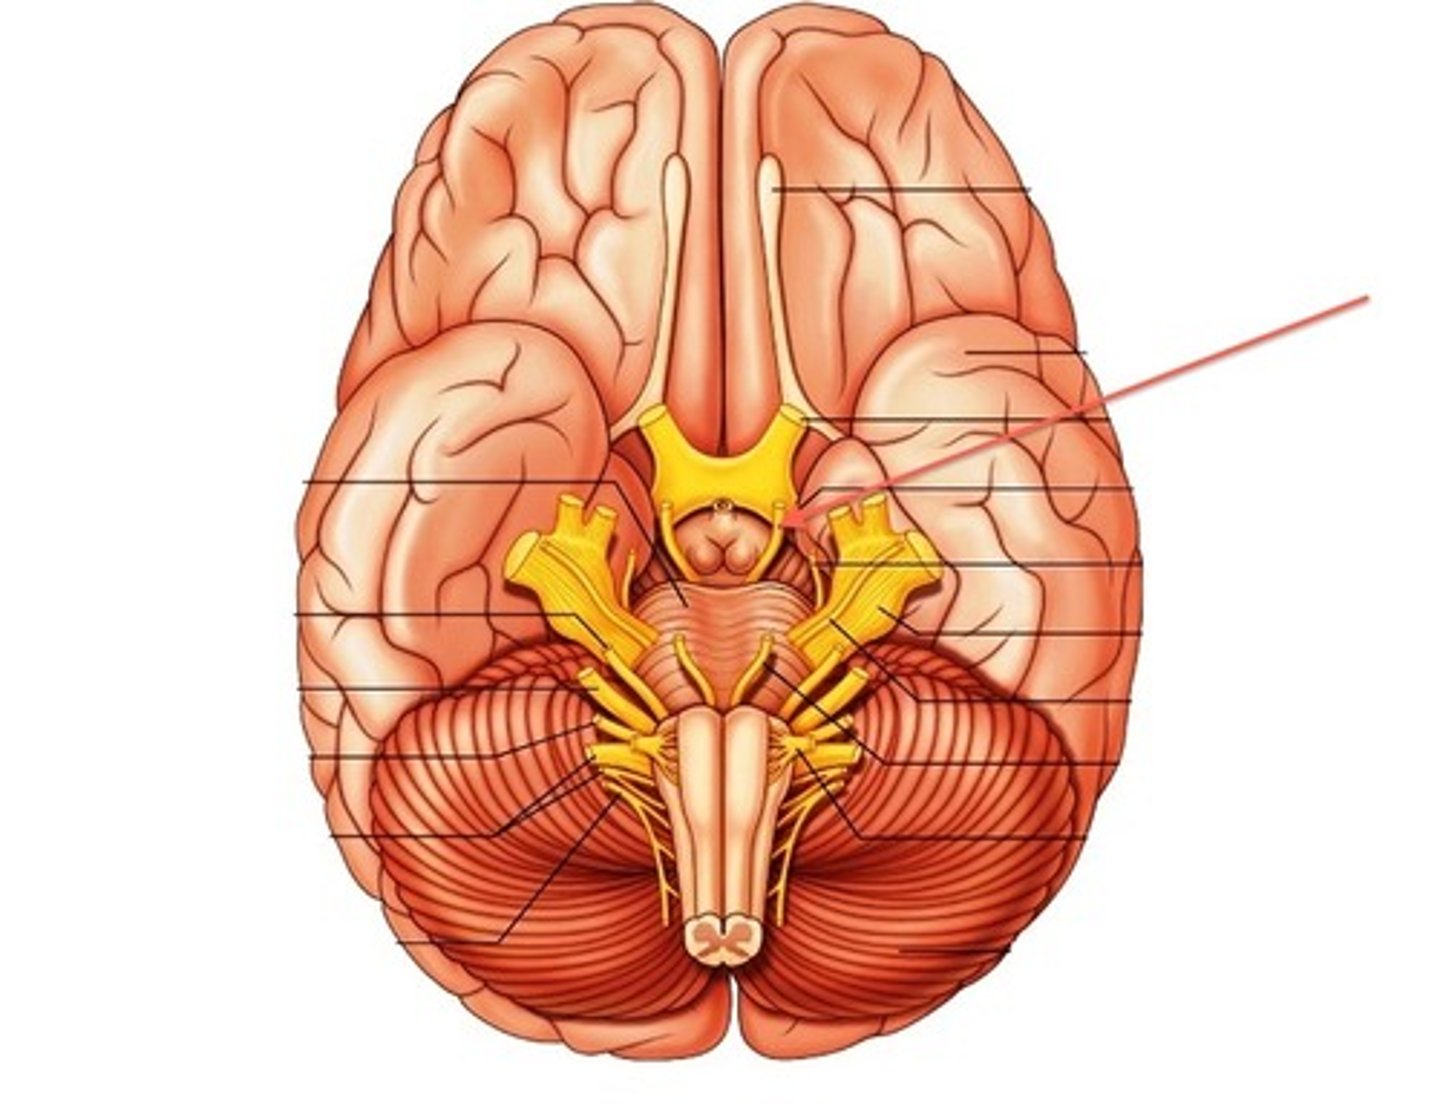

optic nerves (cranial nerve II)

optic chiasma

optic tracts

infundibulum

pituitary gland

mammillary bodies

CNIII (oculomotor nerve)